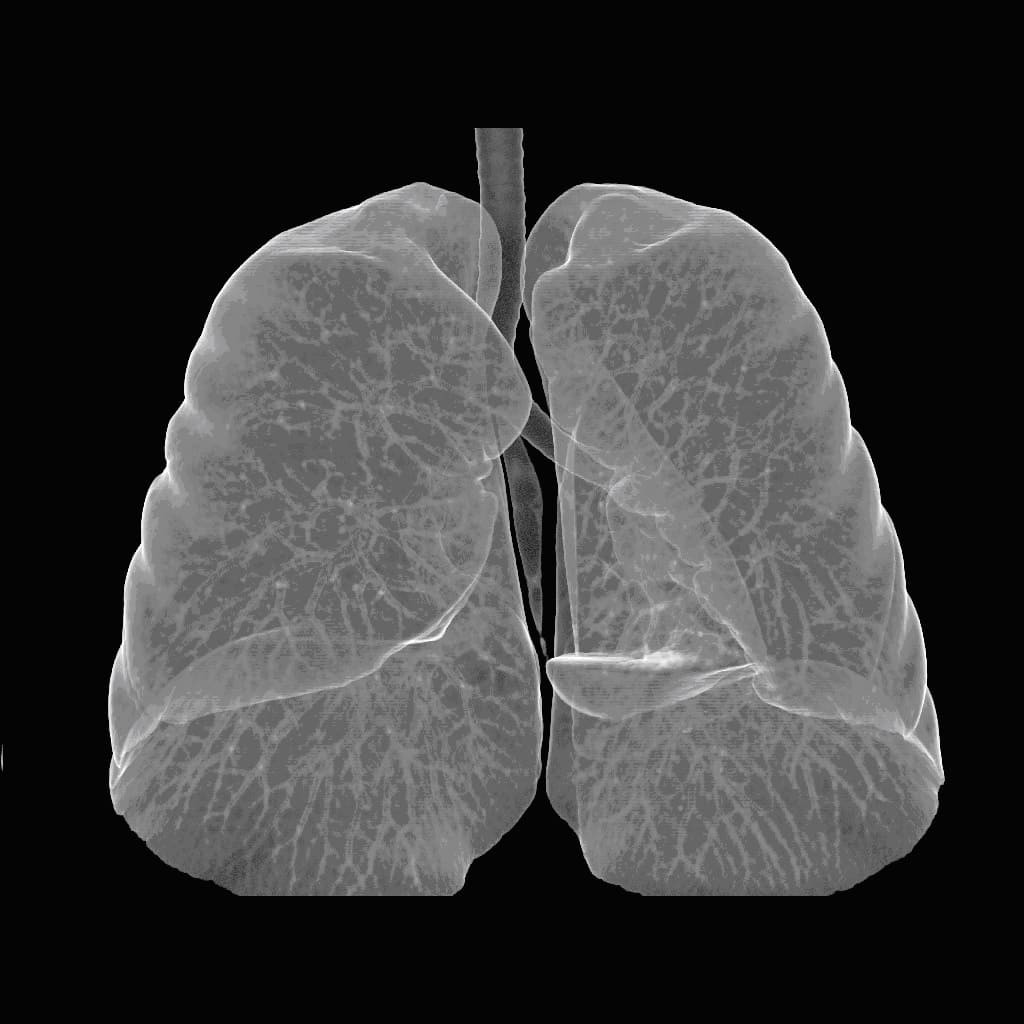

Фотографии и снимки КТ легких без контрастных веществ

Раздел: Визуальный дайджест